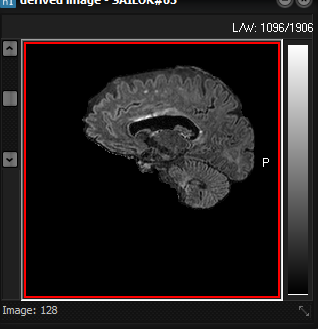

Screenshot

of original 3D volume (left) and resulting brain extracted volume (right)

after preforming a brain extraction session. The resulting extracted brain volume

overlaid on the original is shown below.